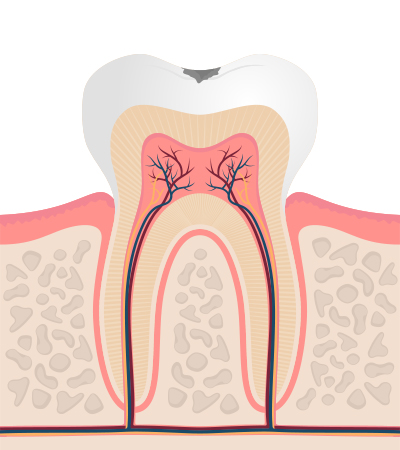

충치의 단계 및 치료법

1단계

법량질까지 진행 증상은 거의 없음